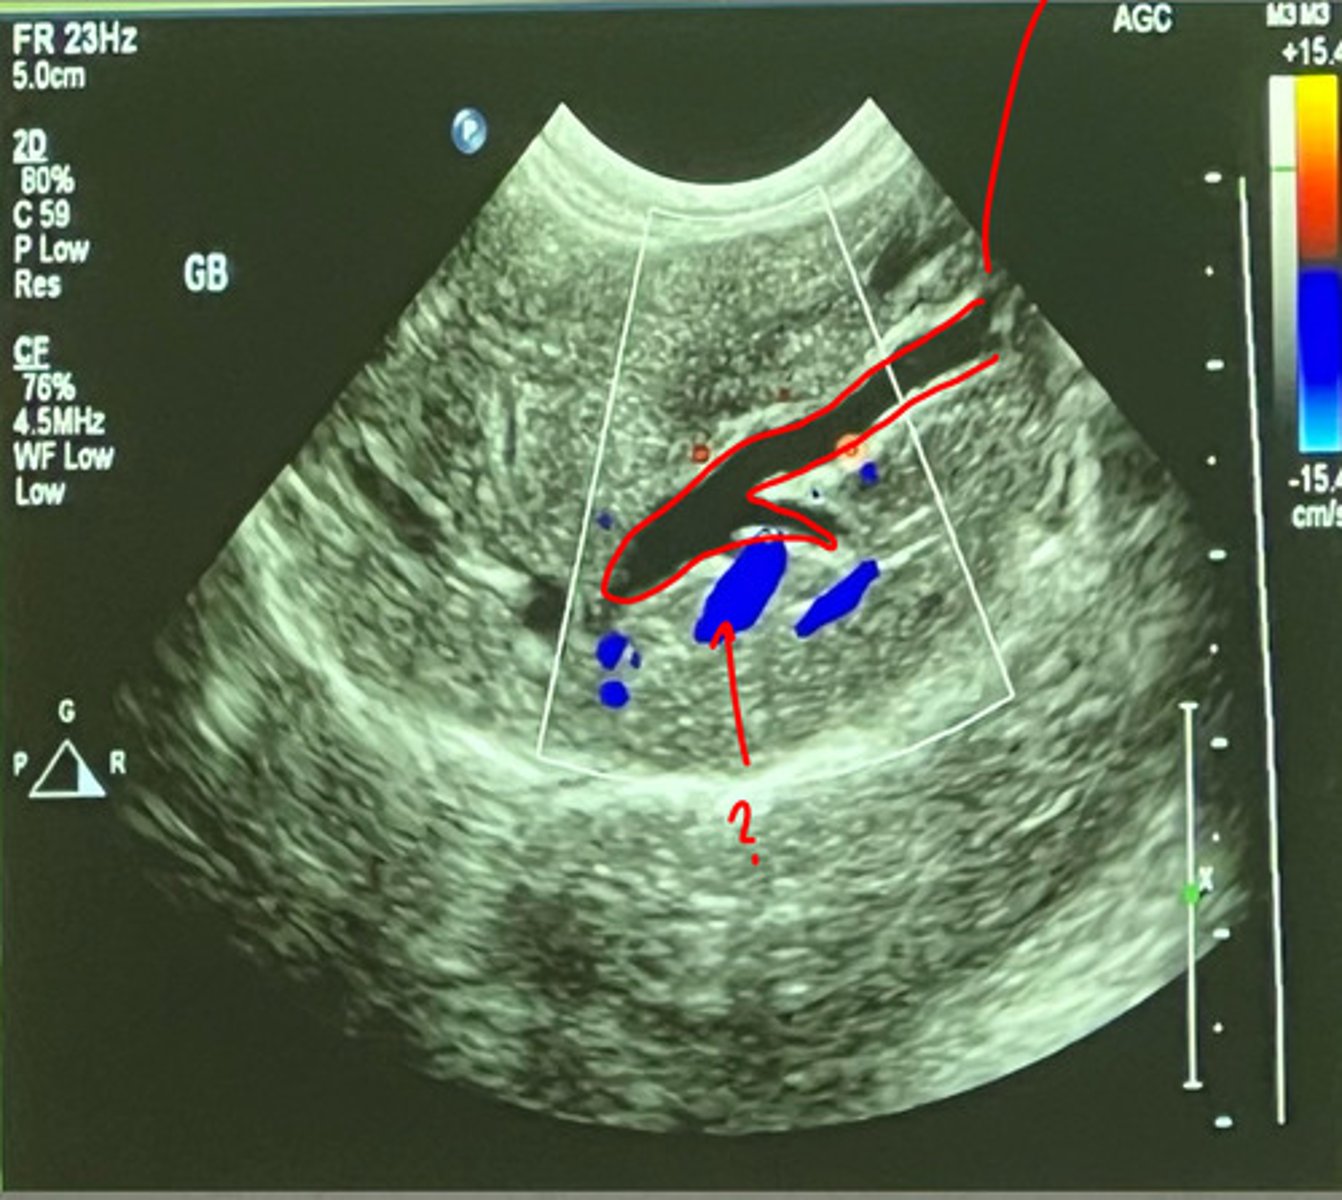

color dopler

what type of tool is being used in this ultrasound to see the different vessels?

portal veins

the _____ veins have the most echogenic walls

at the diaphragm

hepatic veins join the caudal vena cava where?

anechoic

the hepatic veins are what echogenicity?

hepatic veins

do portal veins or hepatic veins have less delineated walls?

hyperechoic

portal veins have a more _______ border than the hepatic veins

left- hepatic vein

right- portal vein

which US shows the portal vein and which is hepatic vein?

hepatic

______ arteries are not detected on 2D images and only found with color flow Doppler

arteries

with color doppler, _______ are the small vascular structures depicted with red color

intrahepatic biliary ducts

which biliary ducts are not normally visualized?

enlarged intrahepatic biliary ducts have _____ blood flow

color Doppler

what tool can be used to help distinguish an enlarged intrahepatic biliary duct from a blood vessel

intrahepatic biliary duct

what duct is being shown with the red outline?